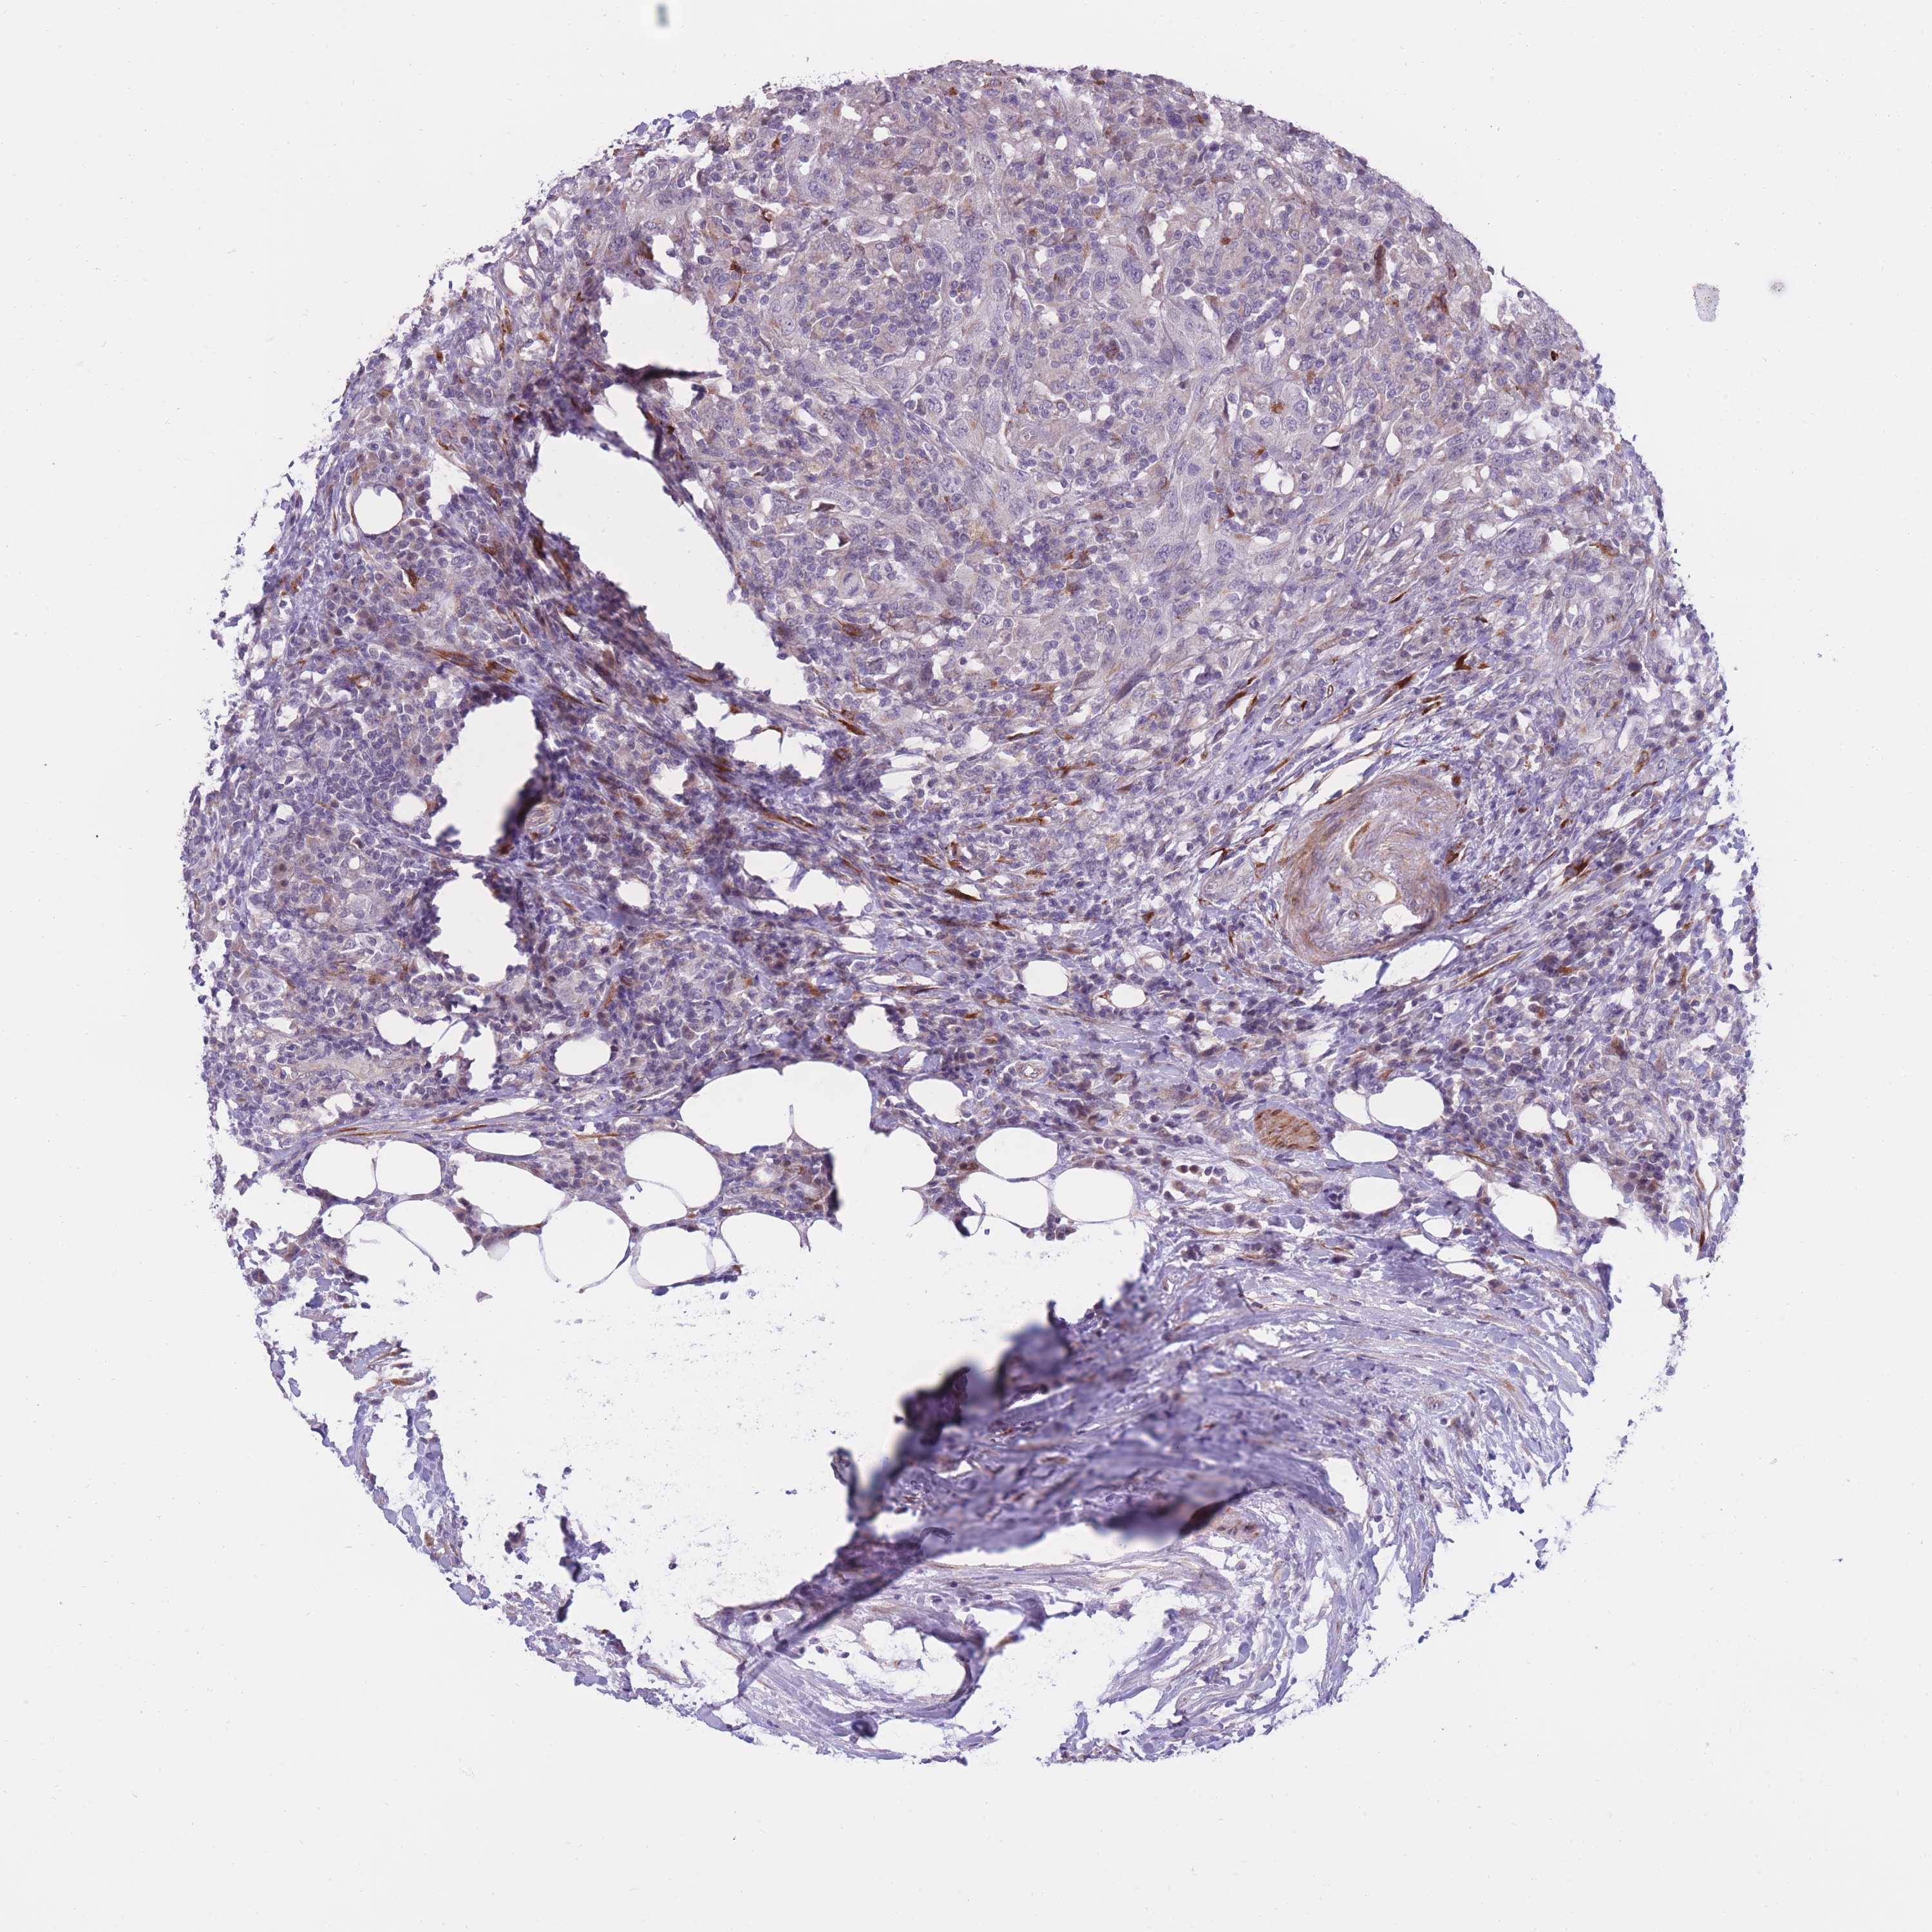

UROTHELIAL CANCER - Protein expressioni

A mouse-over function shows sample information and annotation data. Click on an image to view it in a full screen mode. Samples can be filtered based on level of antibody staining by selecting one or several of the following categories: high, medium, low and not detected. The assay and annotation is described here.

Note that samples used for immunohistochemistry by the Human Protein Atlas do not correspond to samples in the TCGA dataset.

Antibody stainingi

Antibody staining in the annotated cell types in the current human tissue is reported as not detected, low, medium, or high, based on conventional immunohistochemistry profiling in selected tissues. This score is based on the combination of the staining intensity and fraction of stained cells.

Each image is clickable and will lead to virtual microscopy that enables deeper exploration of all samples and also displays staining intensity scores, fraction scores and subcellular localization as well as patient and tissue information for each sample.

Antibody HPA050137

Staining

High

Medium

Low

Not detected

Intensity

Strong

Moderate

Weak

Negative

Quantity

>75%

75%-25%

<25%

None

Location

Nuclear

Cytoplasmic/membranous

Cytoplasmic/membranous,nuclear

Urothelial carcinoma, Low grade

Urothelial carcinoma, High grade

Urothelial carcinoma, NOS